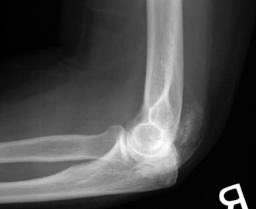

Myositis Ossificans

وهو تجمع دموي يصير حول المفصل الي فيه كسر ممايسبب تكوّن كتلة عظمية تقفل المفصل جزئيا او بشكل كامل، وهي شائعة عند كسور الأطفال واكثر مفصل تصير فيه Elbow Joint.

ملاحظة احياناً بعض المرضى الي يدلكون مكان الكسر ويسوون مساج عليه يكون سبب في حصول هالحالة لهم ⚠️